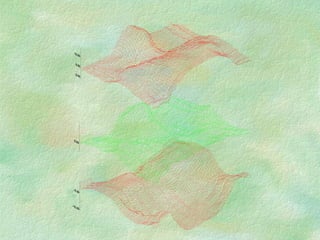

Example: neck: compensateto give uniform dose along midplane throughout treatment field

Example: neck: compensate to give uniform dose along midplane throughout treatment field

Uncompensated Compensated 15-20% <5%